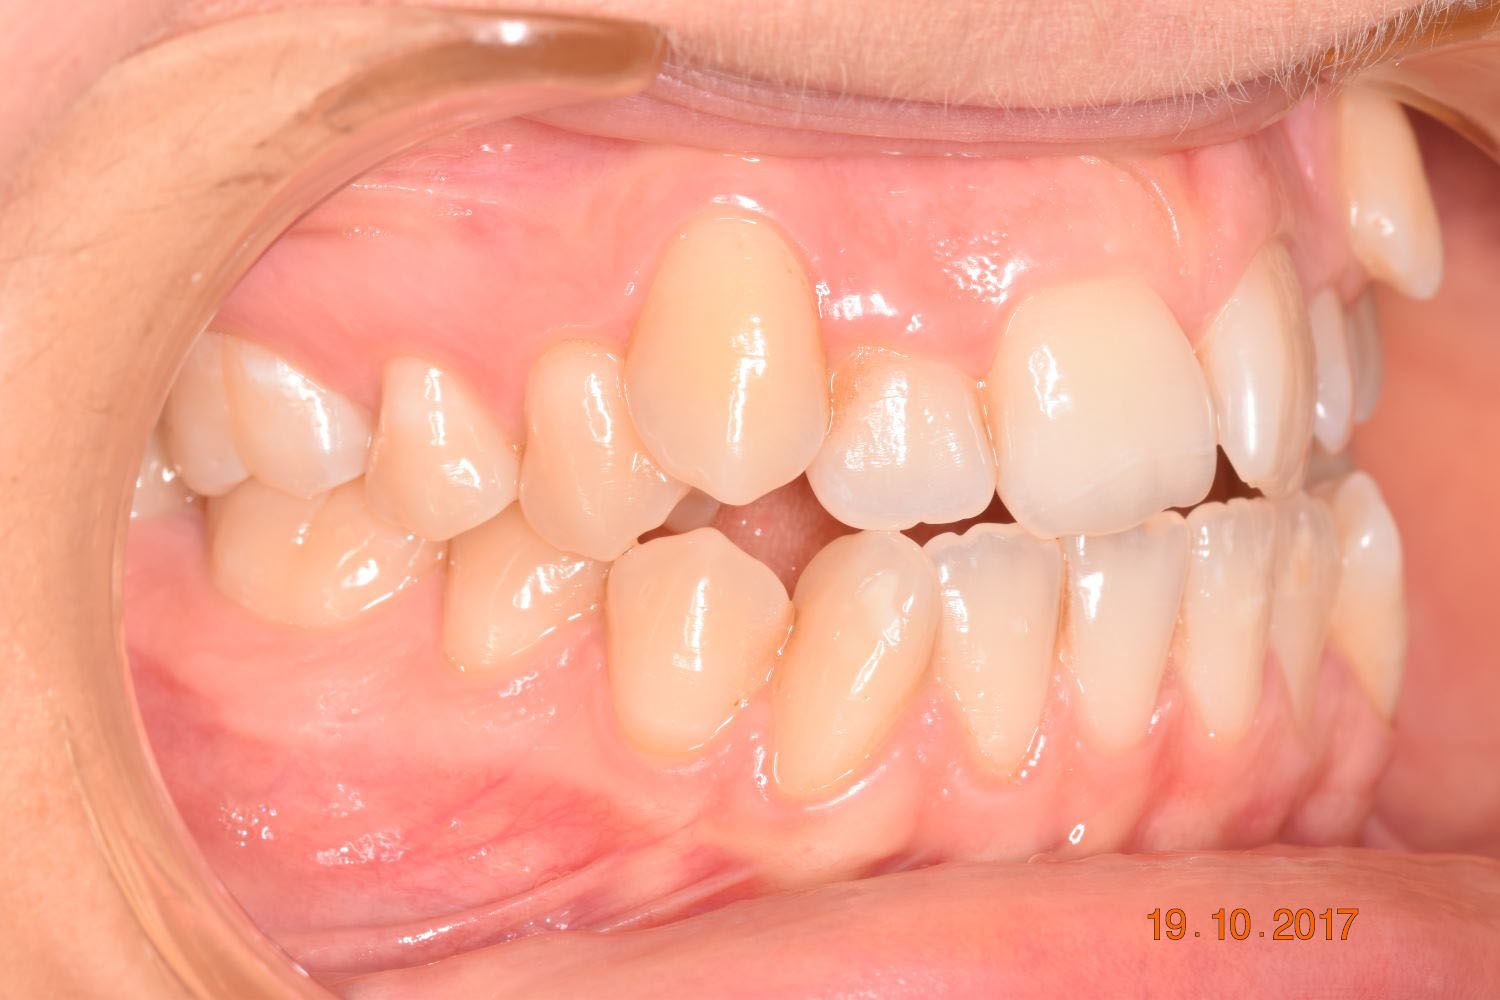

A 27-year-old female patient presented with class III malocclusion, 15 mm crowding in the upper arch, an anterior open bite, a lateral crossbite, and a total ABO score of 29. Her facial profile was straight with a retrusive maxilla, and the upper and lower incisors were retroclined. An extreme lack of midface support was also noted, and the constricted dental arches resulted in a poor smile width and dark buccal corridors. No myofunctional investigations were performed at the time, as they were initially considered unnecessary.

Adhering to the principles of Face First Orthodontics, the primary objective was to increase midface support by expanding the upper maxilla, fixing the cross bite, and aligning the teeth. Closing the open bite was a secondary objective.